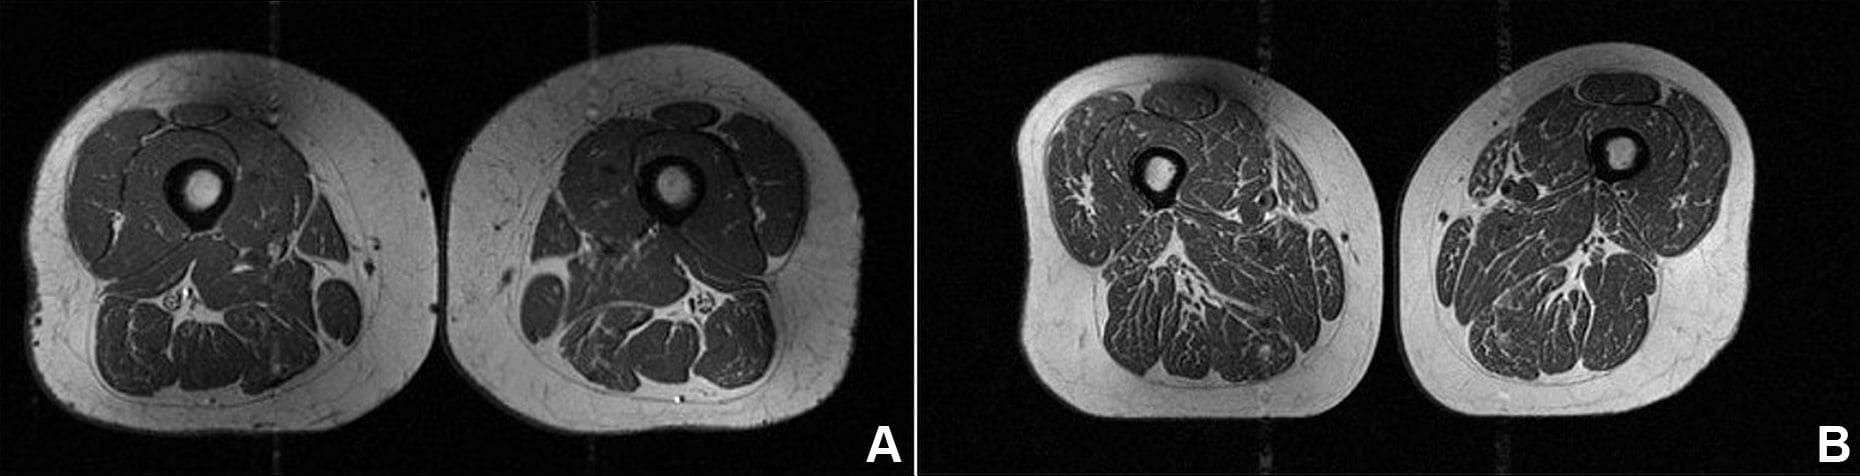

كانت المرأة البالغة من العمر 61 عامًا، التي شكّلت الأطعمة فائقة المعالجة 29.5% من نظامها الغذائي (في الصورة A)، تمتلك مؤشر كتلة جسم أعلى قليلًا بلغ 32.6، وتمارس نشاطًا بدنيًا أقل بكثير من المرأة الأخرى (في الصورة B) التي بلغ مؤشر كتلة جسمها 31.8، وشكّلت الأطعمة فائقة المعالجة 87.1% من نظامها الغذائي.

ومع ذلك، أظهرت المرأة ذات الاستهلاك الأعلى لهذه الأطعمة ترخيمًا دهنيًا أكبر بكثير في عضلات فخذها.

وأشار الدكتور توماس لينك، رئيس قسم الأشعة العضلية الهيكلية بقسم الأشعة والتصوير الطبي الحيوي في جامعة كاليفورنيا، سان فرانسيسكو، إلى أن كمية السعرات الحرارية لم تكن العامل الحاسم.

وقال: "طوال الدراسة، لاحظنا أنّه كلما زاد استهلاك الشخص للأطعمة فائقة المعالجة، زادت كمية الدهون داخل عضلات الفخذ لديه، بغض النظر عن إجمالي السعرات الحرارية".